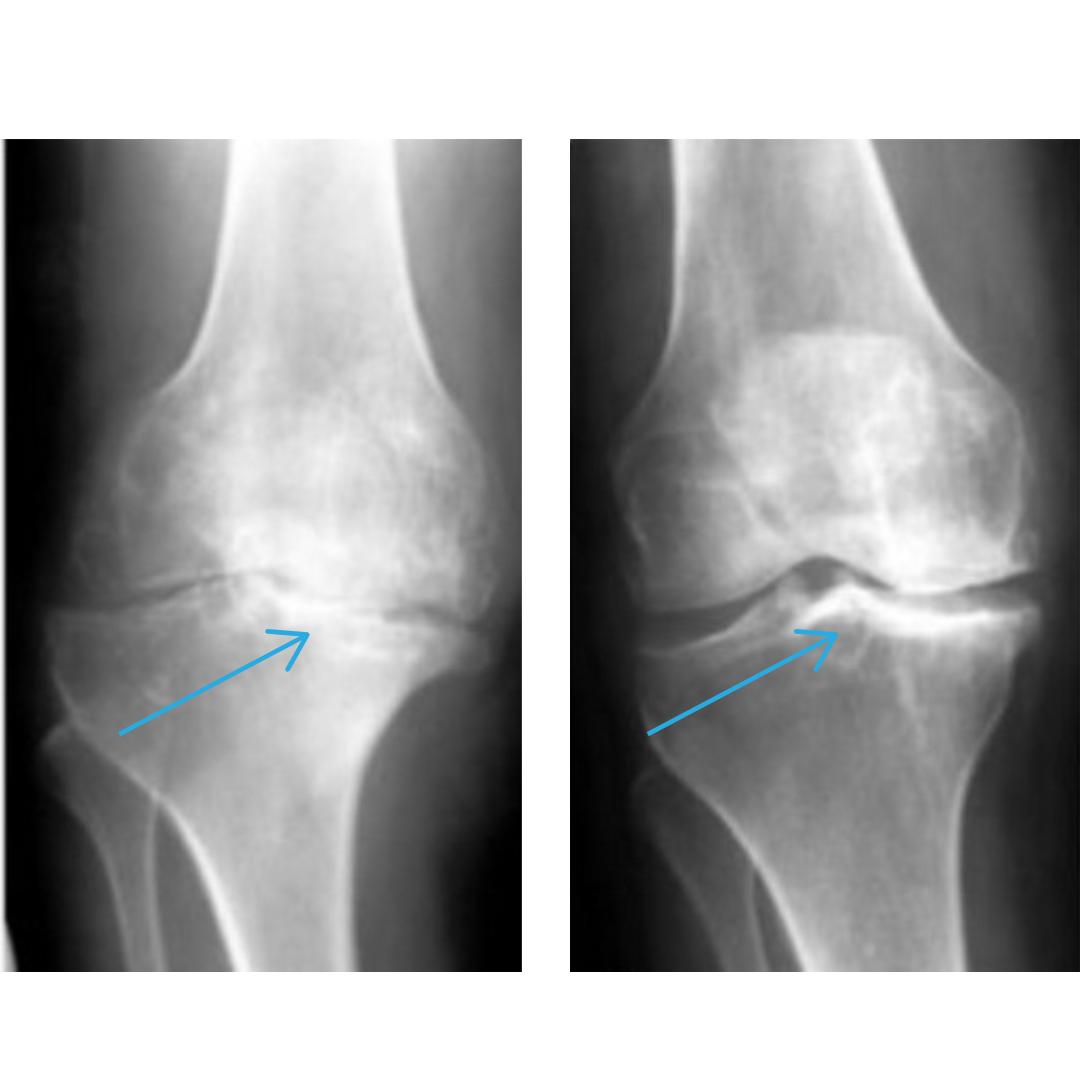

Коли суглоб або міжхребцевий диск пошкоджується, він не може самостійно відновитися. Хрящова тканина руйнується, а без неї кістки починають тертися одна об одну, викликаючи біль, запалення та обмеження рухів.

Натрапила на цей метод зовсім випадково, коли шукала щось ефективне для чоловіка він вже кілька років страждав від болю в коліні. Постійні обмеження в русі, набряки, іноді навіть вночі не міг нормально спати. 😞 Після курсу цього методу результат перевершив усі очікування! На знімках чітко видно різницю суглоб став рухливішим, біль зник, і він нарешті повернувся до нормального життя без операцій та уколів. Рекомендую всім, хто зіштовхнувся з подібною проблемою! Не тягніть, як ми, бо здоров’я - найцінніше в такий важкий час🙏